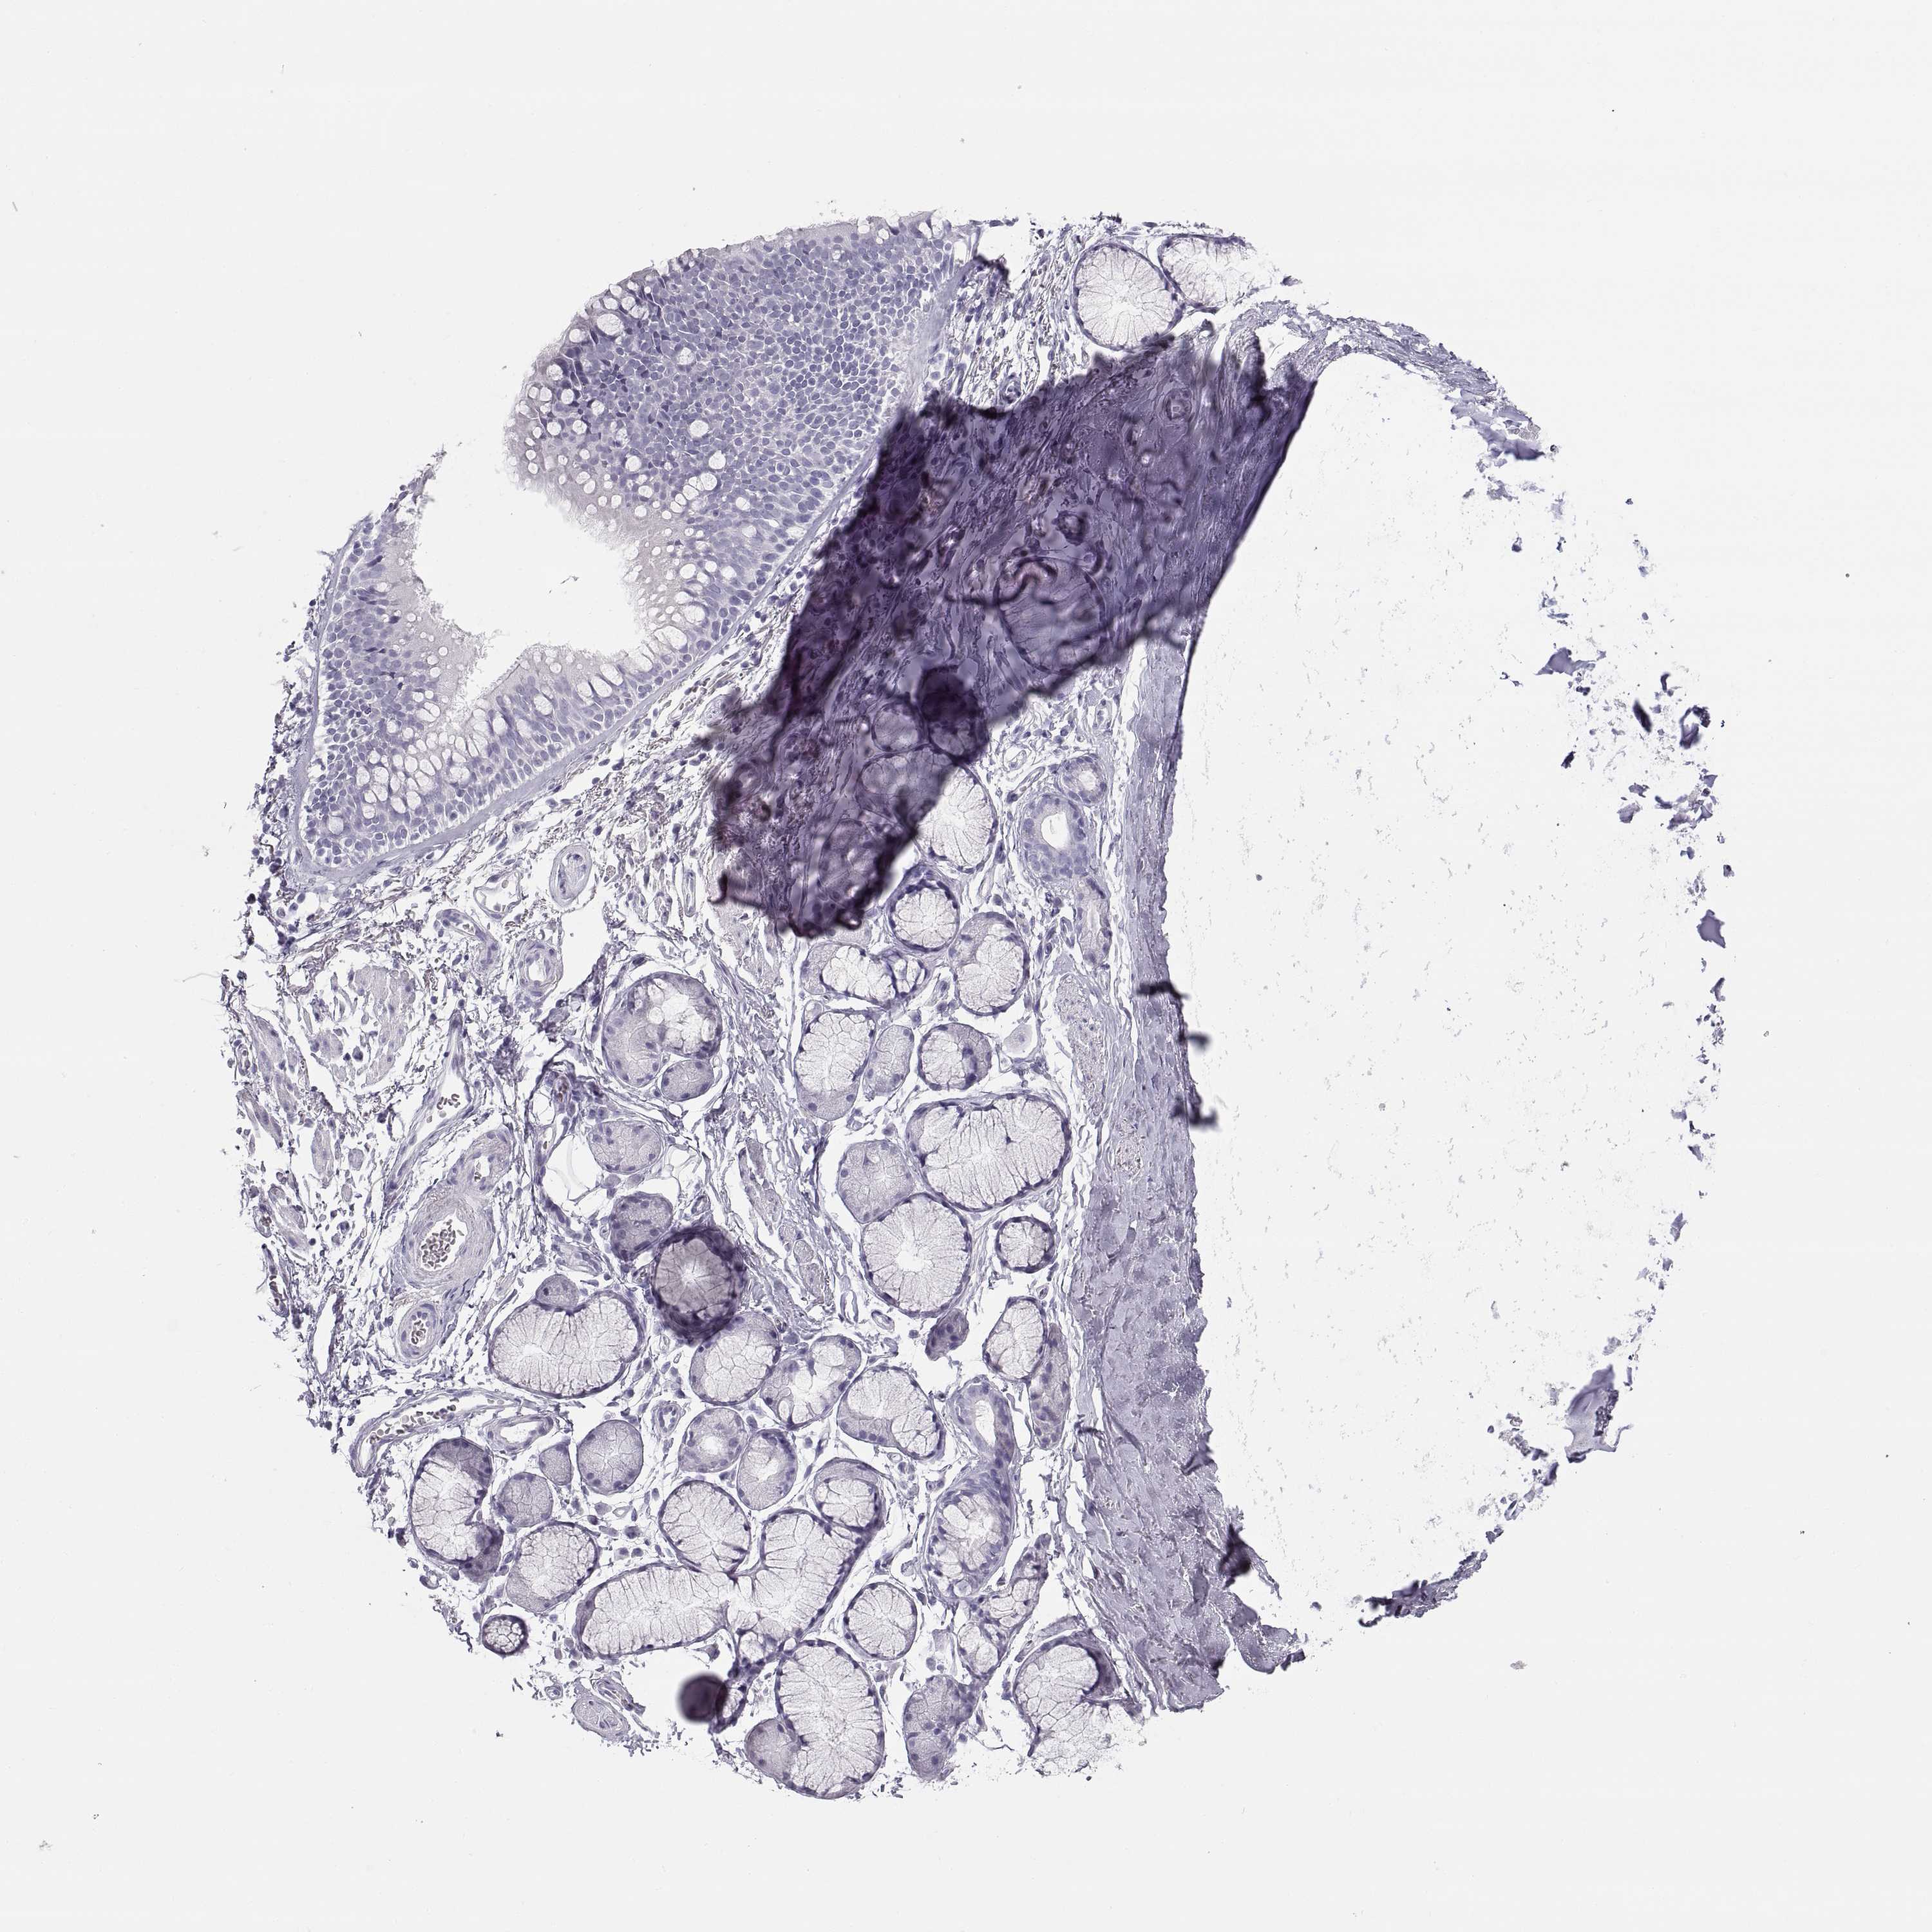

ADIPOSE TISSUE - Antibody stainingi

Antibody staining in the annotated cell types in the current human tissue is reported as not detected, low, medium, or high, based on conventional immunohistochemistry profiling in selected tissues. This score is based on the combination of the staining intensity and fraction of stained cells.

Each image is clickable and will lead to virtual microscopy that enables deeper exploration of all samples and also displays staining intensity scores, fraction scores and subcellular localization as well as patient and tissue information for each sample.

Antibody HPA042476Antibody HPA064892

Adipocytes Not detectedNot detected